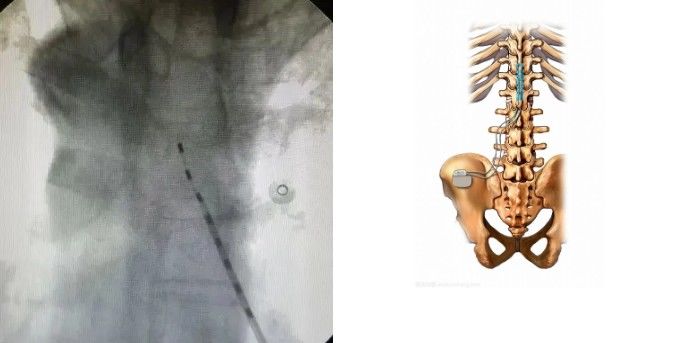

而这位“热心街坊”并没有劝高大叔上医院就诊而是给了他“秘方”然而这“秘方”一用问题却接二连三出现了……高大叔的疼痛感不但没有消失有一天还突然晕倒在地被送到上述医院ICU进行治疗医生检查发现高大叔本身有冠心病、糖尿病等基础疾病加上相信偏方没及时科学治疗导致问题这么严重找到根源后医生安排高大叔接受脊髓电刺激术(SCS)治疗经过10几天治疗高大叔也已经痊愈出院